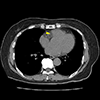

![]() |

LIVER CT(3P) 3상 간 CT 조영제를 주입한 뒤 동맥기, 문맥기, 지연기 세 단계로 간을 촬영해 간암, 전이암, 혈관 이상 등 간 병변을 정밀하게 평가하는 검사입니다. |